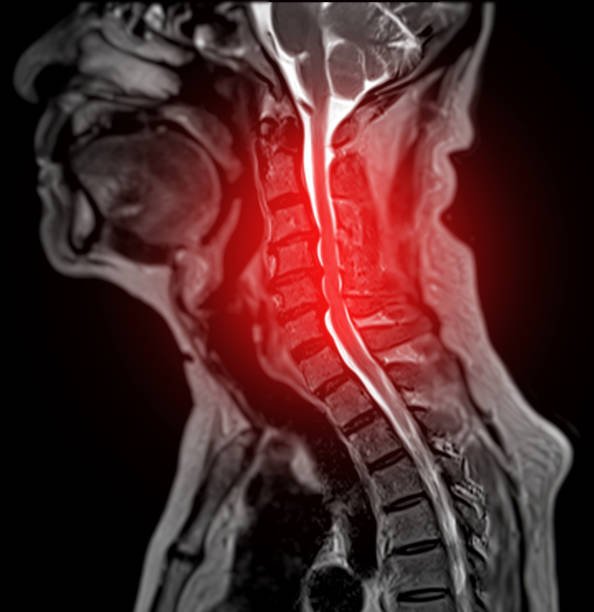

MRI scan of cervical spine showing inflammation and nerve compression requiring cervical spondylosis treatment